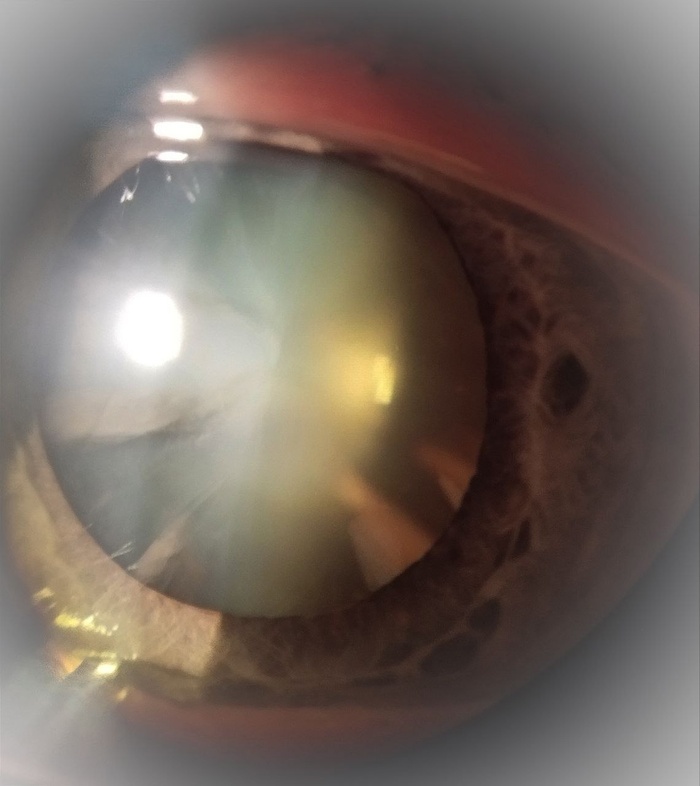

Конечно, волокнам хрусталика бы перестать расти в какой-то момент, но они это делают потому, что рост запрограммирован природой. Когда плотность волокон в хрусталике становится настолько высокой, что транспорт жидкости и обмен веществ становятся невозможными, хрусталик мутнеет. Это и есть возрастная катаракта - она развивается у всех, рано или поздно. Катаракта - это не болезнь, это физиологическое состояние, соответствующее определенному возрасту. Но, современному человеку с его зрительными потребностями это помутнение мешает жить, потому что мешает видеть .

Осмотр на щелевой лампе - это аппарат, похожий на микроскоп, который светит Вам в глаз в то время, когда доктор им двигает и смотрит с другой стороны. Опытный офтальмолог может понять очень и очень многое о Ваших глазах, при помощи этого прибора.

Большое значение имеет состояние хрусталика - чем он плотнее, тем мощнее будет работа ультразвука. Крепкость связок, на которых держится хрусталик тоже оценивается за щелевой лампой, но тут, конечно, возможны сюрпризы, на операционном столе.

Когда на приёме я объясняю пациентам, что человек с катарактой смотрит на мир "как через морозные узоры на стекле", это конечно метафора, но при этом вполне правдоподобная - данные природные картины очень схожи, просто в глазу этот прекрасный рисунок создаётся медленно и всю жизнь, поэтому тот, кто смотрит сквозь него не сразу обращает внимание на помутнение.